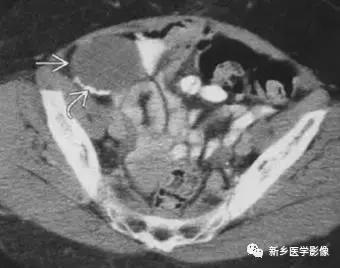

4、腹部切口和注射部位

主要见于皮下脂肪层内,臀部多见。腹部平片有时候会误诊为腹腔病变。